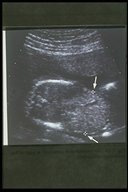

The abdominal wall defect can be diagnosed prenatally by ultrasonography